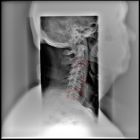

Лечение заболеваний суставов и позвоночника